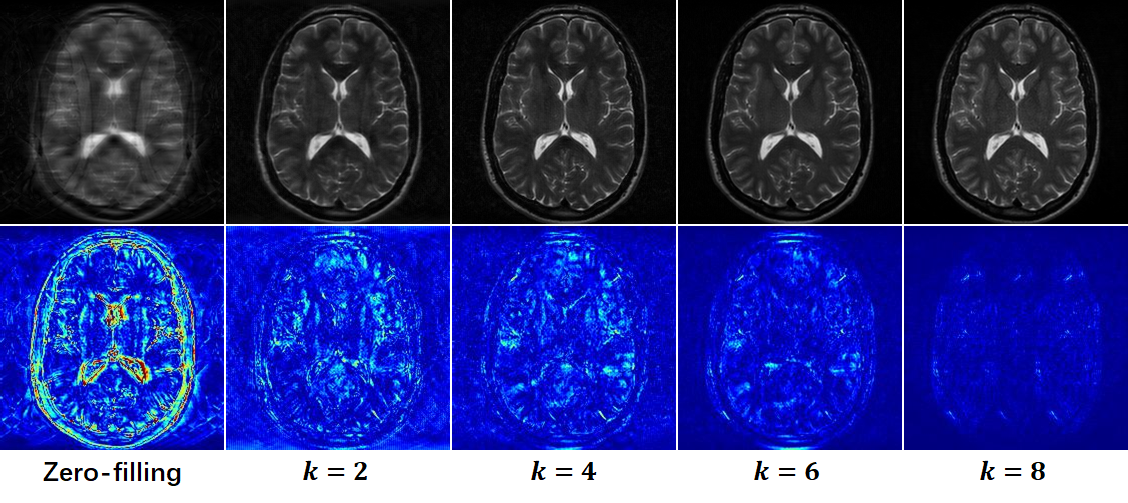

In this section, we conduct a model verification experiment to demonstrate the reconstruction results of the proposed DUN-CP-PPA under different stages. As shown in Fig. 8, it is evident that as the number of stages increases, the image quality improves. These results validate the design of our optimization-inspired iterative network, and the re-visible dual-domain self-supervised learning framework enables the proposed DUN-CP-PPA to achieve the expected MRI reconstruction. Furthermore, our network demonstrates superior transparency compared to other methods.